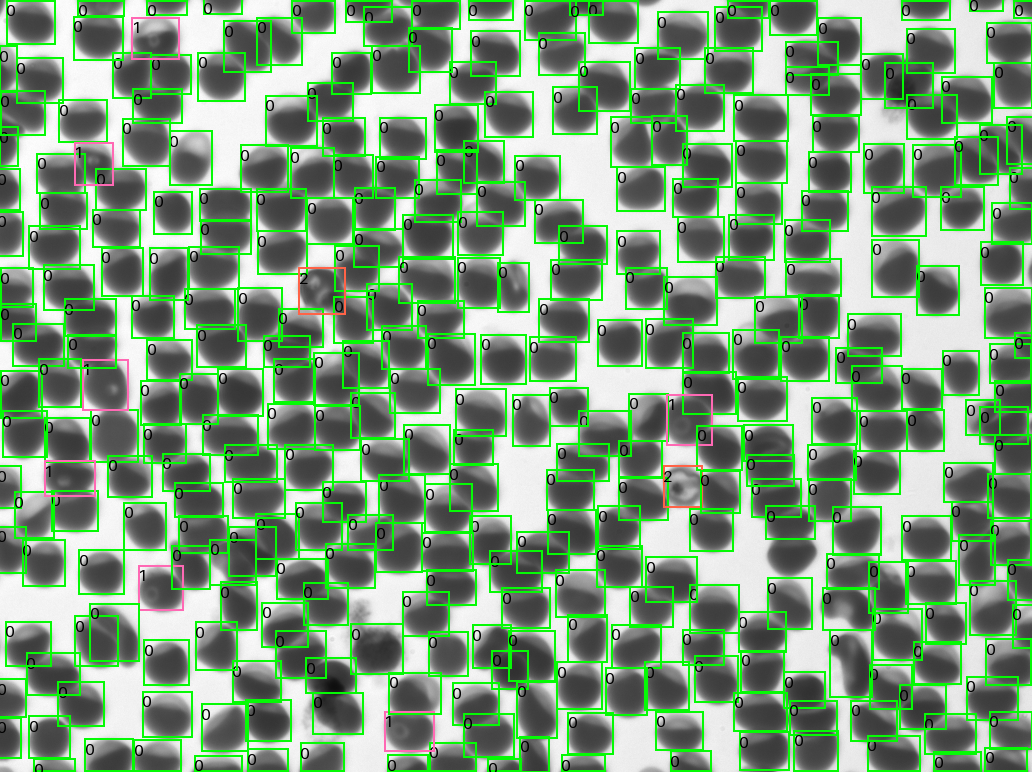

Conceived and developed at CZ Biohub SF, the Remoscope is a fully automated imaging cytometer that can image and count red blood cells, then use machine learning to classify cells as either healthy or harboring malaria parasites, all without the need for fixation or staining. Remoscope can even automatically classify infected cells by the parasites’ various life stages. Results from the field testing, in which Remoscope was used to analyze blood samples from more than 500 individuals in eastern Uganda, showed that it performed nearly as well as the conventional diagnostic technique, which has been in use for more than a century, and Lebel feels confident its accuracy can be improved.

The software is trained to recognize four life-cycle stages of Plasmodium falciparum, the parasite responsible for 90% of malaria deaths worldwide, in red blood cells, including ring, trophozoite, schizont, and gametocyte. Lebel says it should be possible to train the algorithm to recognize other malaria species as well, but that has not yet been tested.

The device is able to image and classify 2 million cells in 12 minutes, meaning the test result can be available in as little as 1 minute, compared to at least 45 minutes for Giemsa staining.